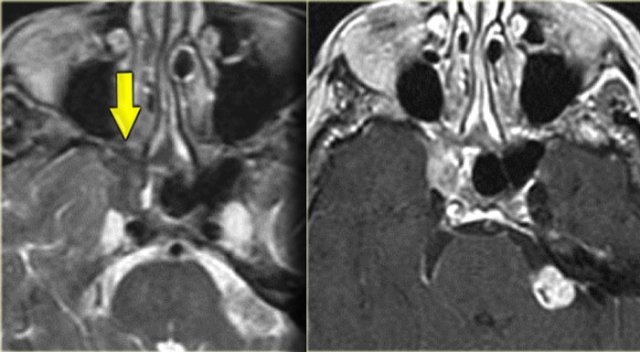

On the left images of a 64-yrs-old, immuno-competent patient, who had a follow-up scan for left-sided vestibular neuroma.

On the image on the left hypointense tissue is seen in the pterygo-palatine fossa and videan canal (yellow arrow).

On the image on the right, which is more cranial, there is hypointense tissue in the pterygo-maxillary fissure and pterygo-palatine fossa.

Continue with the contrast-enhanced T1W-image.

Sinonasal carcinoma Sinonasal carcinoma

There is solid enhancement of the abnormality.

The differential diagnosis again consists of 2 catagories: neoplasm and chronic invasive fungal infection.

In an immuno-competent patient, a neoplasm is much more likely.

Continue with the CT-images.

This is the corresponding CT, performed not to make the diagnosis, but to assess the condition of the adjacent bony structures, especially the sphenoid sinus.

Also, it serves to guide the endoscopist for intraoperative biospy.

There is extensive destruction of the skull base.

The coronal image illustrates a normal foramen rotundum on the left (yellow arrow), which on the right has been obliterated by soft tissue.

There is extensive bone destruction, and a possible area for biopsy is indicated by the blue arrow.

At biopsy the diagnosis of a spindle cell carcinoma was made.